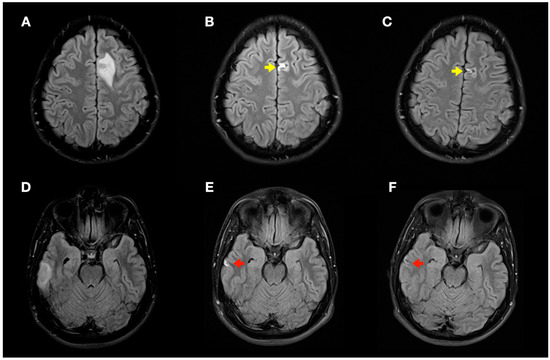

During follow-up, the patient did not present any new neurological symptoms, and radiological improvement was observed in successive neuroimaging tests (Figure 6), with only minimal chronic cortical lesions compatible with areas of cerebral malacia in the right temporal and left frontal lobes of the brain.

Figure 6.

Radiological evolution of lesions secondary to decompression sickness: axial FLAIR images. (A,D) Initial images: left frontal cortico-subcortical hyperintense lesion (A) and right temporal cortico-subcortical hyperintense lesion (D). (B,E) Image control at 1 month: minimal hyperintense lesions in the right temporal (red arrow) and left frontal (yellow arrow) lobes of the brain. (C,F) Image control at 4 months: minimal chronic lesions compatible with cerebral malacia in the right temporal (red arrow) and left frontal (yellow arrow) lobes of the brain.

Finally, in our case, control MRI (1 and 4 months after DCS) demonstrated resolution of the hyperintense bihemispheric vasogenic edema lesions on T2WI/FLAIR sequences and the ADC map, with only minimal areas of cerebral malacia persisting.